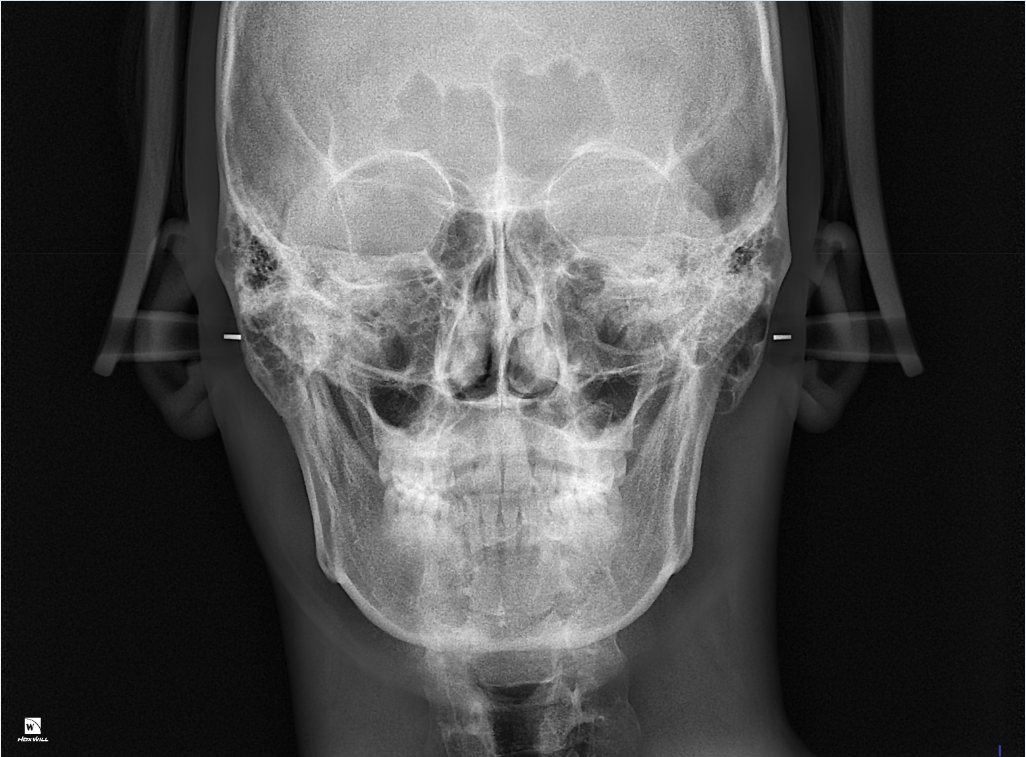

• 2번 째 사진

그냥 지내셔도 됩니다. 교정한다고 하더라도 중심선 정확히 맞추기 어렵습니다. x-ray 골격 사진상으로도 이정도면

거의 비대칭이 없다고 해도 무방합니다.